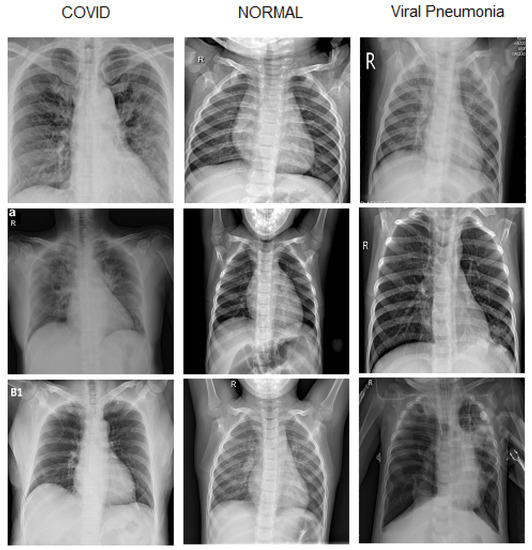

2.1. Dataset Preparation